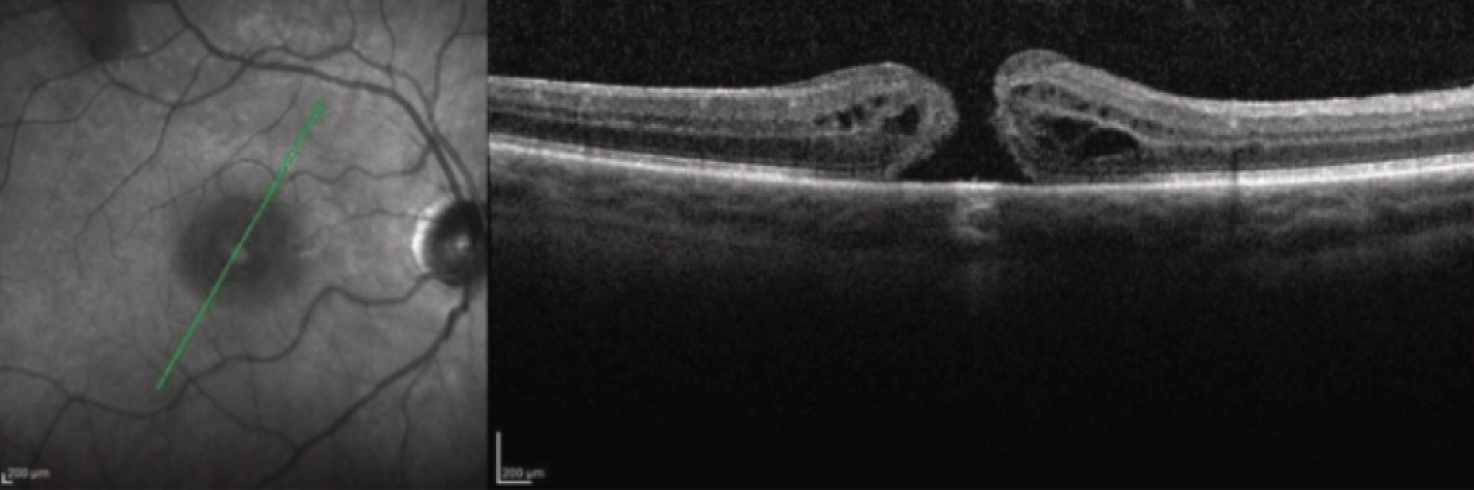

A macular hole is a full-thickness tissue defect that produces a gray or black spot in the macula. The macula is a small area in the center of the retina that is responsible for straight-ahead or focused vision. The very center of the macula is also the thinnest part of the retina, making it susceptible to holes, particularly as a person ages.

Although a macular hole may gradually enlarge, peripheral vision remains, and straight-ahead vision is almost never completely lost. Most macular holes develop as a result of the vitreous gel pulling on the delicate macular tissue. Unlike tears in the peripheral retina, a macular hole does not typically lead to retinal detachment.